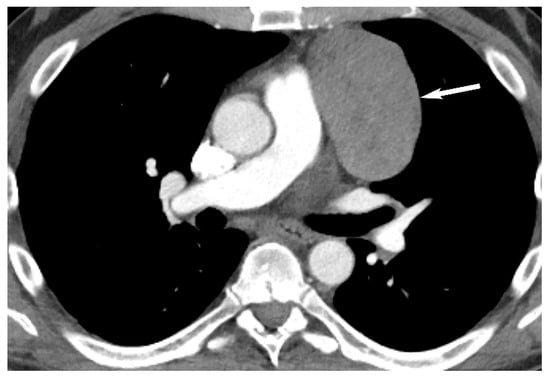

5. Thymic Epithelial Neoplasms

7. Germ Cell Tumors

9. Hypervascular Lesions